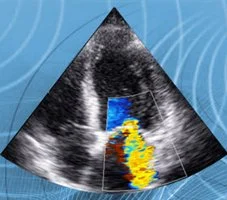

Doppler transcranico (con mezzo di contrasto): per la ricerca della pervietà del forame ovale molto spesso associato alle forme di emicrania con aura o alla cefalea a grappolo